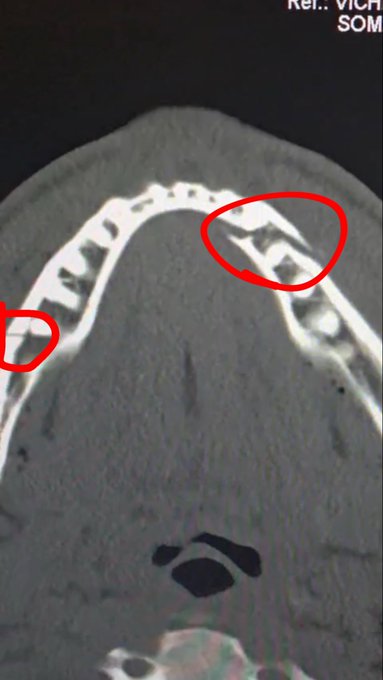

Eerder op de dag deelde Paul op X al röntgenfoto's waarop de breuken duidelijk te zien waren. Het verklaart ook waarom hij tijdens het interview na het gevecht - waar hij nog stoer probeerde te doen - meerdere malen moest stoppen om bloed uit te spugen. Dat was geen theaterbloed, dat was pure interne schade.

De details van de operatie liegen er niet om. "Twee titaniumplaten aan elke kant. En er zijn enkele tanden verwijderd," biecht Paul op via Instagram. Laten we dat even tot ons door laten dringen. Joshua heeft hem zo hard geraakt, dat zijn kaak letterlijk met metaal weer aan elkaar moest worden gezet. En die tanden? Die zijn helemaal losgeslagen door Joshua - een échte bokser.